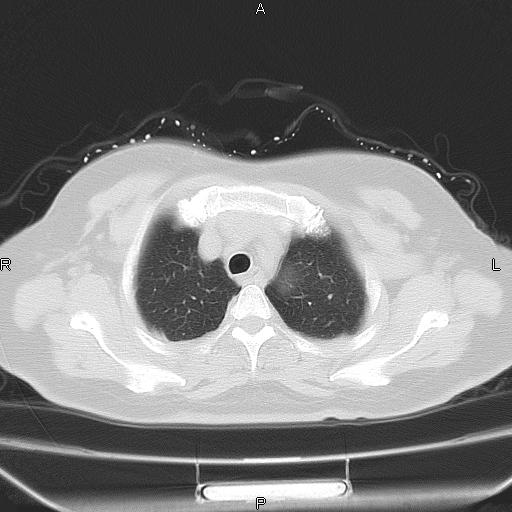

女、63Y 双眼睑下垂,早轻晚重。 胸腺瘤???

结果胸腺瘤